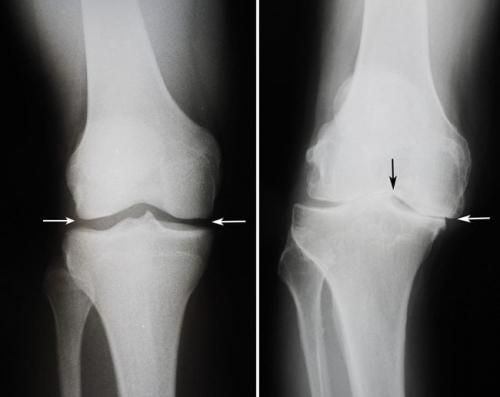

Некоторые суставы в своем составе, кроме основных, имеют дополнительные приспособления, такие как диски или мениски. Классификация суставов называет их комплексными. Диски разделяют полость сустава на две части, образуя тем самым "этажность" соединения. Мениски имеют вид полумесяца. Оба приспособления обеспечивают соответствие прилегающих форм хрящей в суставной сумке относительно друг друга.

Внутрисуставные хрящи — диски, мениски, хрящевые губы — увеличивают конгруэнтность (т. е. соответствие) суставных поверхностей сочленяющихся костей. Эти элементы сустава человека также играют роль в амортизации движений. Вместе с тем диски и, отчасти, мениски подразделяют полость сустава на два отдела, каждый из которых допускает свои движения.